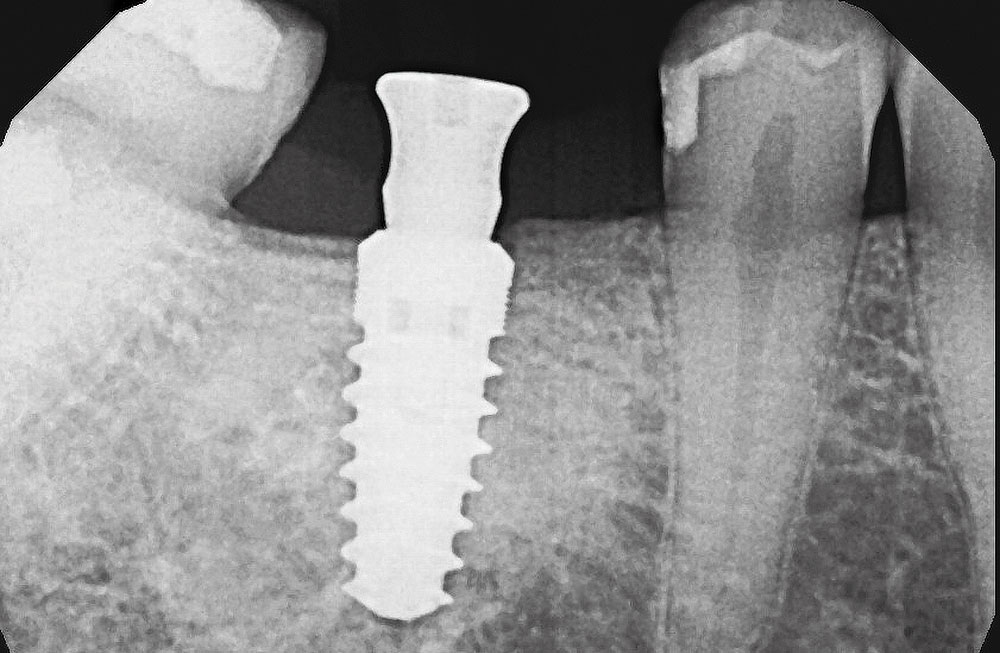

Following well-established clinical research methods, bone loss was measured as the distance from the implant shoulder to the first contact of bone to implant, from both the mesial and distal sides.

Figures 1a, 1b: Calibration of the bone loss measurements was determined by measuring the length of the implant (1a), or by measuring the diameter in cases where the implant apex was not visible (1b).